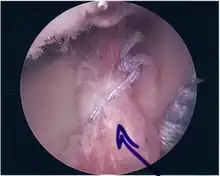

Repair of SLAP tear

Arthroscopic SLAP Lesion (type 2) repair

Following inspection and determination of the extent of injury, the basic labrum repair is as follows.

• The glenoid and labrum are roughened to increase contact surface area and promote re-growth.

• Locations for the bone anchors are selected based on number and severity of tear. A severe tear involving both SLAP and Bankart lesions may require seven anchors. Simple tears may only require one.

• The glenoid is drilled for the anchor implantation.

• Anchors are inserted in the glenoid.

• The suture component of the implant is tied through the labrum and knotted such that the labrum is in tight contact with the glenoid surface.